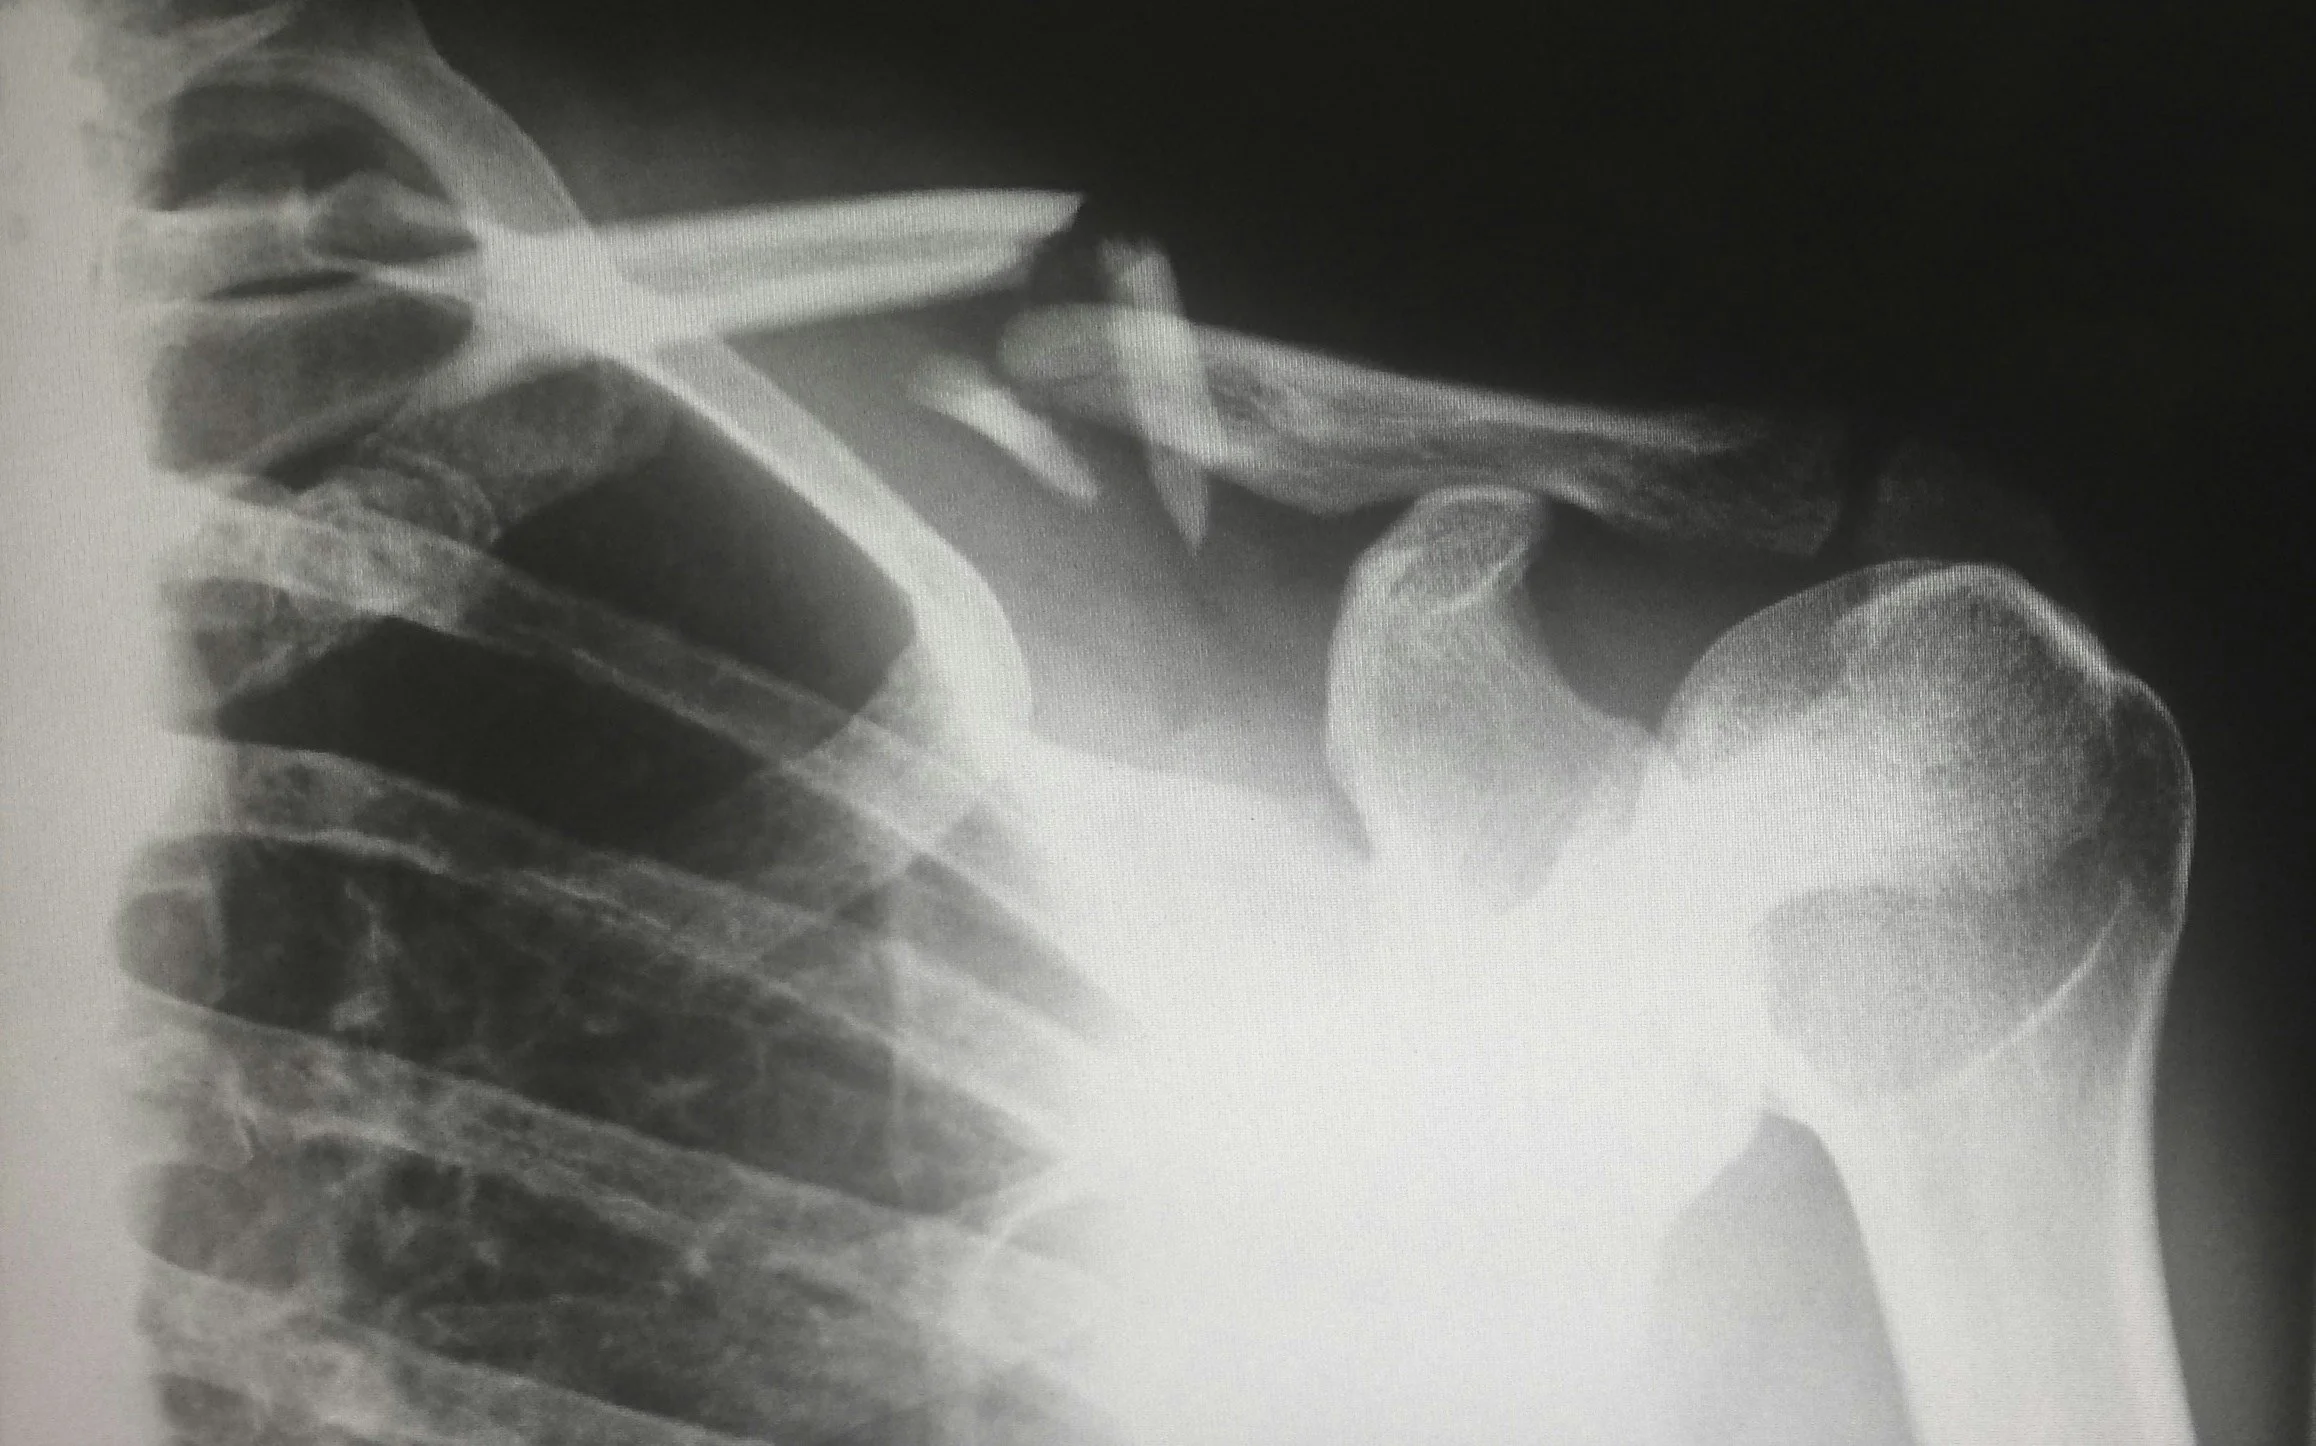

If you’ve got sudden swelling, severe pain, suspected fracture or an acute injury, medical assessment should come first. Red light therapy can be supportive later, once the acute phase is appropriately managed.

Osteoarthritis-related discomfort

A supportive option for stiffness and reactivity linked to degenerative joint change.

Tendon or ligament irritation

Low-load support for overuse discomfort and connective tissue recovery.